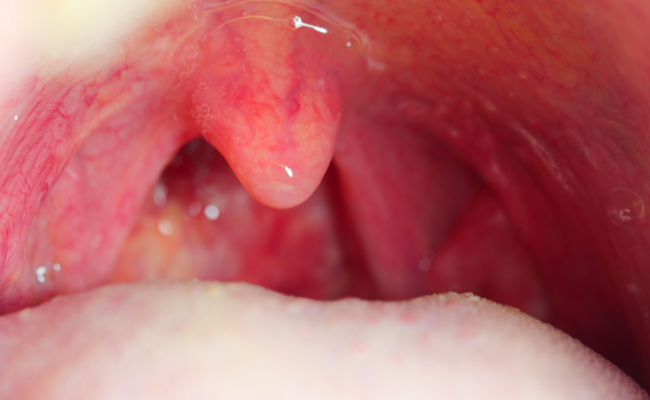

Uvulitis is characterized by the inflammation of the uvula, a small, cone-shaped tissue situated at the back of the throat. It may manifest through symptoms such as swelling, redness, and discomfort. Although generally not a severe health concern, uvulitis can be uncomfortably pronounced and might hint at an underlying issue. The swollen uvula associated with uvulitis serves crucial functions, secreting saliva for mouth lubrication and acting as a barrier against the intrusion of food and liquids into the nasal space. While the irritation caused by a swollen uvula can be bothersome, the reassuring aspect is that uvulitis is typically a temporary condition.

1. Swelling: The uvula may appear larger than usual and may touch the tongue or roof of the mouth.

2. Redness: Inflamed uvula often presents as red or irritated.